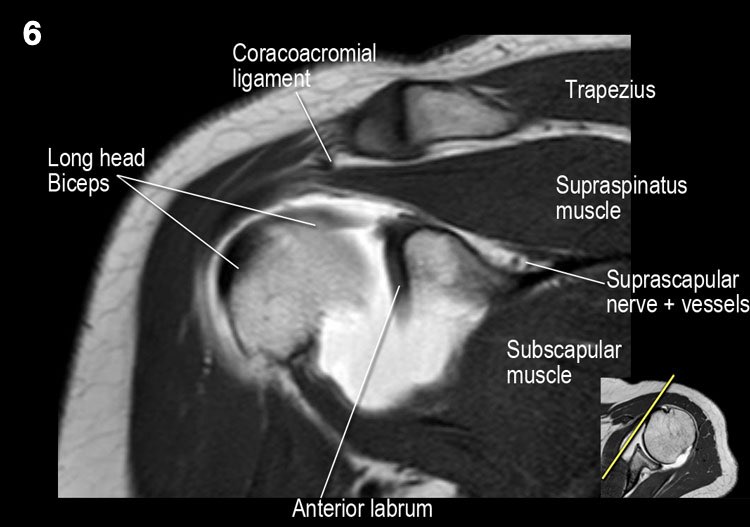

Giải phẫu mặt cắt vành và danh sách kiểm tra

- Lưu ý thần kinh và mạch máu trên vai.

- Đánh giá phức hợp sụn viền-gân cơ nhị đầu phần trên và tìm kiếm túi cùng dưới sụn viền hoặc rách SLAP.

- Tìm kiếm tràn dịch quá mức trong túi hoạt dịch dưới mỏm cùng vai và rách gân cơ trên gai.

- Tìm kiếm rách kiểu “rim-rent” của gân cơ trên gai tại chỗ bám của các thớ sợi trước.

- Đánh giá chỗ bám của dây chằng ổ chảo-cánh tay dưới (IGHL) vào xương cánh tay. Đánh giá phức hợp sụn viền-dây chằng phần dưới. Tìm kiếm tổn thương HAGL (bong điểm bám dây chằng ổ chảo-cánh tay tại xương cánh tay).